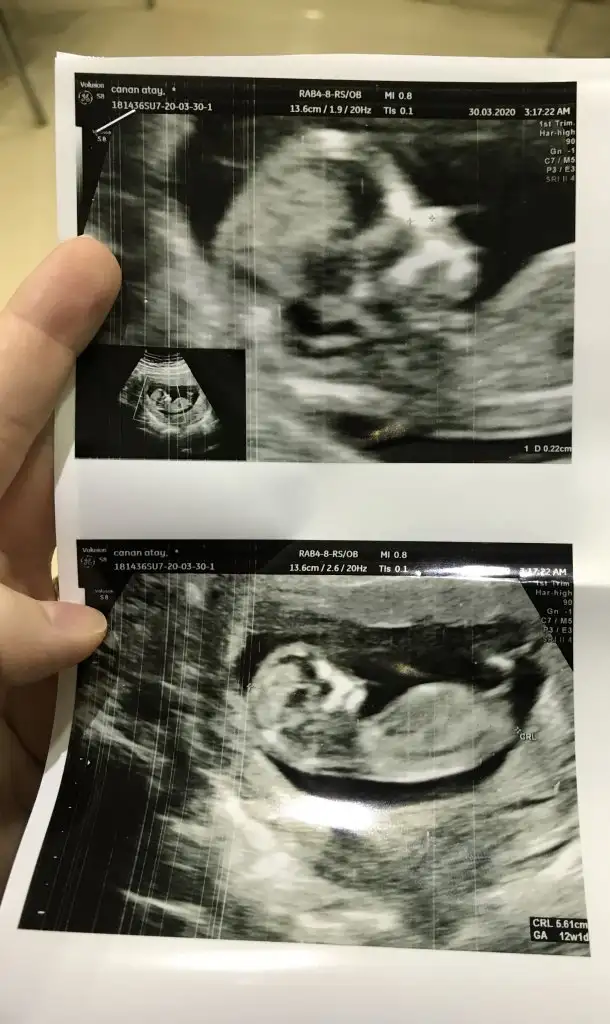

Meraba.12+1 iz cinsiyetini tahmin edebilirmisiniz

Buradaki fotoda 7 haftalıkken.karindan ultrason.bi önceki resimlerde doktor 12 haftalıkken kararsız kaldı.net birşey söyleyemedi.

ikili tarama sonrası. Sizce cinsiyeti nedirr? Doktor bi tahmin de bulundu ama daha erken tabi ☺️☺️

ikili tarama sonrası. Sizce cinsiyeti nedirr? Doktor bi tahmin de bulundu ama daha erken tabi ☺☺

Usg net değil emin olmadım başka usg de paylaşın 12 13 hafta olursa şimdilik sanki erkek gibi gibi 😬

Kız sanki burada nubu ne dik nede paralel karşıya bakıyor 😊 önceki usgde erkek gibiydi 😄

😂 Tahminim kız ama daha tam oluşmamış üç haftası var oluşması icin dedi doktor.tabi ki hayırlısı olsun saglıklı hayırlı evlat olsun ama gönlümden gecen kız olması bakalım bekleyip görücez.tesekkürler tahmininiz için ❤️